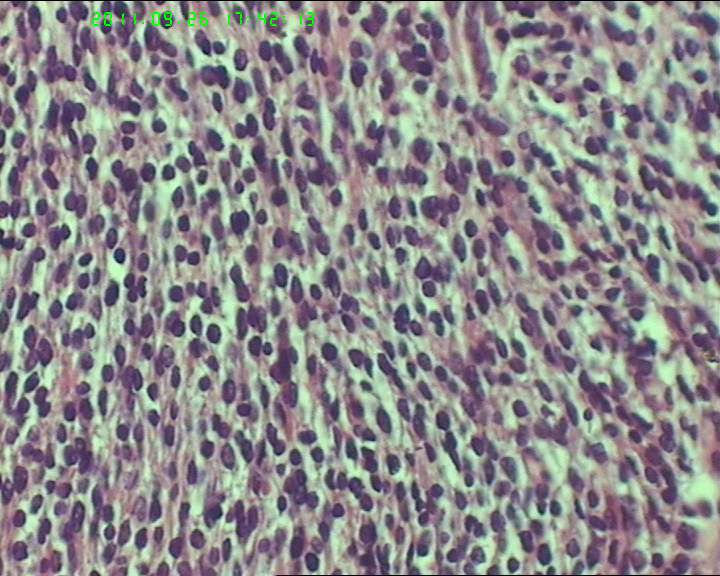

鉴别诊断排排队:1、GIST,2、MPNST,3、去分化脂肪肉瘤,4、恶性间皮瘤,5、恶性SFT,6、平肉

主要考虑前二者。CD34,CD117,S-100,BCL-2,SMA, D2-40,CR, VIM. 结果如何?请楼主揭谜底吧。